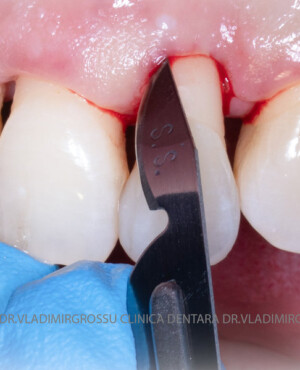

Adiția de gingie (gingivoplastia)

Aditia gingivală este o procedură chirurgicală ce corectează diverse probleme estetice și funcționale, cum ar fi recesiunea gingivală. În implantologia modernă, aditia de țesut moale este utilizată aproape în fiecare intervenție de inserție a implantului dentar pentru a asigura un aspect estetic natural și o bună integrare a implantului în cavitatea bucală.